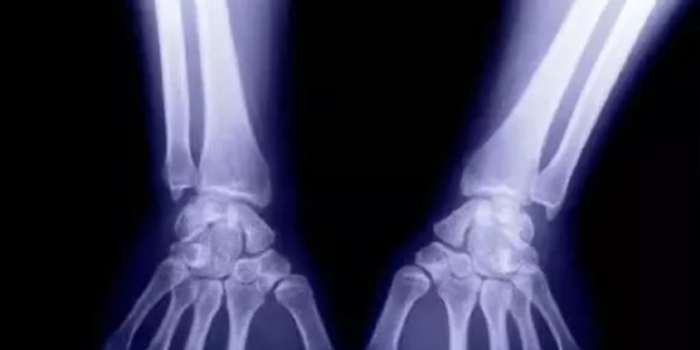

1、外伤骨头——粗看X线片,细看CT,核磁看不清

各种外伤,如果怀疑伤到了骨头,优先选择X光照片,检查结果快速易得。若要进一步观察,可以选择CT。超声、核磁对于骨皮质髓质等看不清,一般不选择。